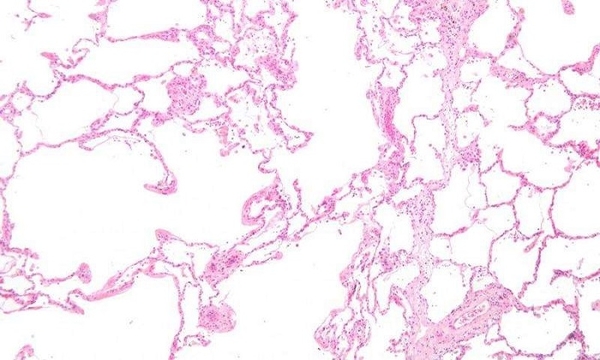

Nhóm nghiên cứu đã phân tích tất cả dữ liệu hình ảnh lâm sàng có sẵn từ gần 3.500 bệnh nhân bị đột quỵ ở vùng Greater Cincinnati/Bắc Kentucky vào năm 2015, đánh giá hình ảnh về dấu hiệu của bệnh lí mạch vành nhỏ trong não dưới dạng chấn thương trước đó, chảy máu rất ít trong não (microbleed), thoái hóa chất trắng ở não (làm mòn mô) hoặc teo não, trong số các quan sát khác. Họ đã xác định được ba cụm đặc điểm hình ảnh có thể quan sát riêng biệt, mỗi cụm có liên quan đến một tập hợp các biến số lâm sàng cụ thể.

Giáo sư Achala Vagal giải thích: "Điều này có thể giúp chúng tôi hiểu được đặc điểm sinh học của sức khỏe não bộ có từ trước ở bệnh nhân đột quỵ và giúp hướng dẫn các can thiệp trong tương lai. Và dự kiến tất cả các thông số hình ảnh về sức khỏe não bộ do bệnh lí mạch vành nhỏ sẽ được tập hợp chặt chẽ, nhưng chúng tôi nhận thấy thiếu sự tập trung của chảy máu rất ít trong não do bệnh thoái hóa chất trắng ở não”. Với kiến thức thu được từ nghiên cứu, nhóm nghiên cứu hiện đang sử dụng dữ liệu hình ảnh sức khỏe não bộ để xây dựng mô hình dự đoán đột quỵ tái phát. Việc mô tả đặc điểm quy mô lớn như vậy về sức khỏe não bộ có từ trước rất hữu ích để xác định đặc điểm mới có thể quan sát được, từ đó có thể hướng dẫn các nghiên cứu tiếp theo.